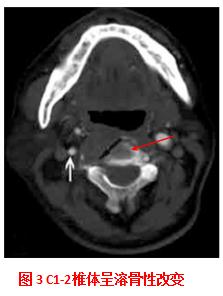

2017年患者出现颈部疼痛,骨扫描示C1-2可见核素浓聚。颈部CT可见对应椎体呈溶骨性改变。穿刺查见鳞癌细胞。

该患者在维持化疗期间出现C1-2椎体骨转移,结合既往治疗情况,给予多西他赛+C225全身治疗。同时,考虑到患者颈部疼痛和颈椎发生病理性骨折易致高位截瘫,给予椎体成形术+放疗。